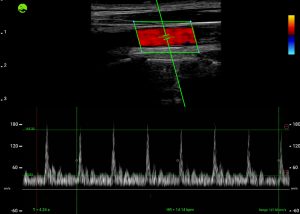

Real-Time Visual Guidance

Dynamic, multi-planar probe positioning assistance overlaid directly on the ultrasound image

Built from a dataset of millions de-identified ultrasound images, our AI models cover Obstetrics, Cardiology, and Gynecology. They analyze key anatomical structures in real time, providing accurate biometric measurements and insights that help clinicians assess fetal growth, cardiac function, and organ health with greater speed and confidence.